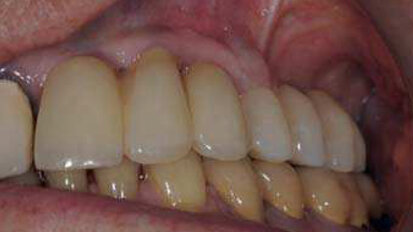

Entre BOPT et BTA : Une étude de cas sur le remodelage du contour gingival de restaurations dento-portées au moyen de couronnes provisoires en résine.

Le remodelage du contour des tissus mous péri-implantaires au moyen de couronnes provisoires en résine après la pose d’un implant...